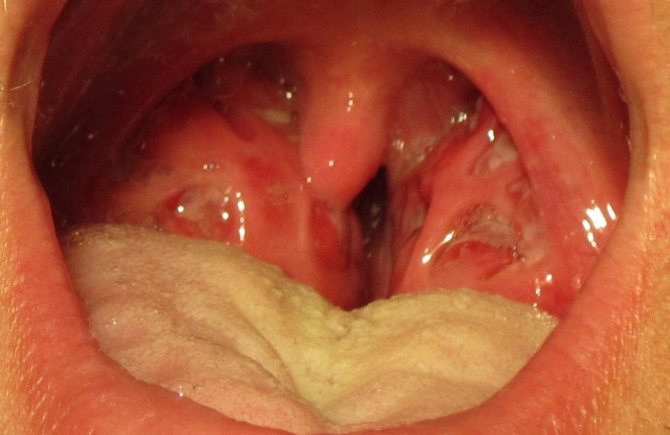

При обследовании становятся видны увеличение, отек миндалин, слизисто-гнойные выделения, белый налет с желтыми вкраплениями на слизистой оболочке и гнойные воспаления фолликулов. Воспаляются и начинают сильно болеть (особенно при пальпации) лимфатические узлы в верхних шейных отделах. В некоторых случаях наблюдается легкая отечность сосочков языка (его еще называют «земляничный язычок»).

На фото можно увидеть типичные для лакунарной ангины гнойные островки.